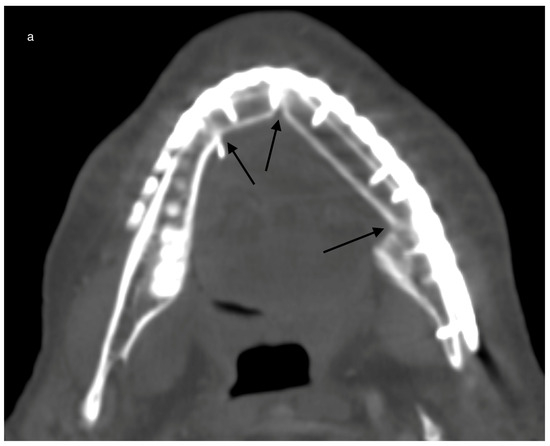

Figure 4.

Example for ossification in CT scans over time in a case with a primary reconstructed mandible after malignant tumor resection and post-reconstructive adjuvant radiotherapy (postORT): Example for a reconstructed mandible with a 2-segmented fibula 265 days after operation. All three contact points are marked with black arrows (a). Slow progression of ossification (black arrows) after 494 days (b).